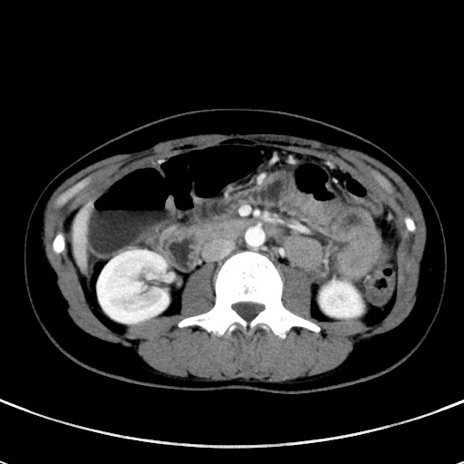

冠状断像

【症例】20歳代女性

【主訴】嘔吐、下腹部痛

【現病歴】昨日夕食後に嘔吐し下腹部痛が出現。本日になっても嘔吐持続し改善しないため来院。

【身体所見】意識清明、BT 37.2℃、BP 108/67mmHg、腹部:平坦、やや硬、下腹部正中から右にかけて圧痛あり、反跳痛軽度あり、tapping pain(+)。

【データ】WBC 13600、CRP 14.94